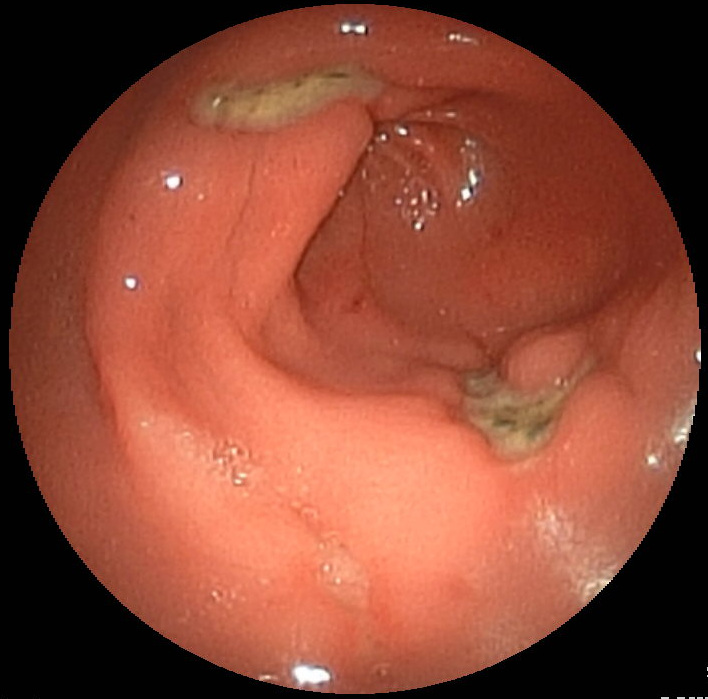

It was very difficult to find reliable data about the occurence of peptic ulcers. Studies done on kids differ widely in their results. One study found that 56 out of 694 children who went to have an upper gastrointestinal endoscopy. This study is not entirely appropriate because it only included children that already were suspected to have some sort of gastric disease and because the study was run for only one month. Another study found that between 1997 and 2000 peptic ulcers occured in 30.35% of studied cases, while between 2007 and 2010 20.19% of cases where found to have peptic ulcers. This study was a meta study. However, the frequency is relatively high and did not really give me the information I was looking for. A review on the topic of stomach ulcers I found stated a study that used population-wide gastro-enteroscopies (sending a little camera down the oesophagus into the stomach), which found a prevalence of 4.1%. I consulted a book I have been using quite a bit these days called "Lehrbuch der Inneren Medizin" by Siegenthaler et al. In chapter 12 "Krankheiten des Verdauungstraktes" (diseases of the digestive tract), they state that roughly 7% of the "working, male population" had stomach ulcers at one point in their life. What about women? And unemployed people? Well, I had to visit organizational websites, like that of the NHS. Here they state that 1 in 10 (so 10%) of people will have a peptic ulcer at some point in their life. Because this seems to be some sort of guessing game, let´s say that 7% of people will have to deal with a stomach ulcer once in their life. I am still not satisfied. And here is why.

All of this has not been known until the 80s, when Dr. Marshall and Dr. Warren started to work together. They successfully isolated the weirdly looking bacteria from patients with gastric ulcer. Since Dr. Marshall was still in his training, he had to move to other hospitals, which stalled the progress on the joint project. Once Marshall found a position at a local hospital in Perth, the work continued. By that time Marshall and Warren had gained some support internationally, but also criticism. Dr. Marshall in particular received a lot of criticism and was struggling to get his hypothesis proven. Unable to reproduce his findings in humans with animal studies (alas giving animals H. pylori cultures and seeing if ulcers develop), people said that his conclusions were premature and that the bacteria were contaminants. At that time Dr. Marshall was already treating patients with antibiotics and bismuth, a cheap treatment that could cure ulcers within two weeks without the need of surgery. In order to get his theory accepted by the wider science community he decided to take a drastic step. He used himself as an animal study and drank an H. pylori culture, after getting a baseline endoscopy done. While he already assumed that he would get an ulcer, he was surprised by how well these results supported his theory. Now that he had shown that H. pylori could cause ulcers, he had to treat himself with antibiotics. Dr. Marshall overcame the infection and soon got funding to perform a double-blind study to investigate whether antibiotics were able to cure stomach ulcers. Although it still took time for his theory to be accepted, the cure for a vast amount of stomach ulcers was found. Dr. Marshall and Dr. Warren were both awarded a Nobel prize in 2005.